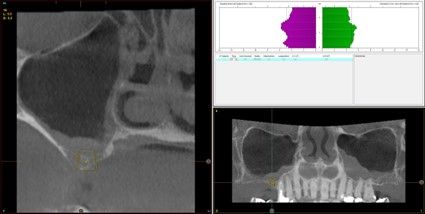

Material y método. Se ha llevado a cabo un estudio retrospectivo de pacientes tratados mediante implantes extracortos (5,5 y 6,5 mm de longitud) colocados mediante elevación transcrestal sin el uso de injerto. Como variables principales se han estudiado: la pérdida ósea crestal de los implantes y la ganancia en altura sobre el ápice. Como variable secundaria se ha estudiado la supervivencia de los implantes.

Resultados. Fueron reclutados 13 pacientes en los que se insertaron 30 implantes. Una vez insertados y cargados los implantes, la altura media final fue de 9,68 mm (+/- 2,66), lo que supone una ganancia promedio de 5 mm. A los 10 años, se observó una disminución media de la altura ósea ganada en los implantes en conjunto de 0, 29 mm (+/- 0,77). La media de la pérdida ósea mesial fue de 0,73 mm (+/- 0,75 mm) y la media de la pérdida ósea distal fue de 0,98 mm (+/- 1,2 mm). La supervivencia fue del 100%.

Material and methods. A retrospective study of patients treated with extra-short implants (5.5 and 6.5 mm in length) placed by transcrestal elevation without the use of a graft was carried out. The main variables studied were: the crestal bone loss of the implants and the gain in height above the apex. Implant survival was studied as a secondary variable.

Results.Thirteen patients were recruited and 30 implants were inserted. Once the implants were inserted and loaded, the mean final height was 9.68 mm (+/- 2.66), which represents an average gain of 5 mm. At 10 years, there was a mean decrease in the overall bone height gain of the implants of 0.29 mm (+/- 0.77). The mean mesial bone loss was 0.73 mm (+/- 0.75 mm) and the mean distal bone loss was 0.98 mm (+/- 1.2 mm). Survival was 100%.

Nuestro grupo de estudio modifica esta técnica de elevación transcrestal utilizando para el acceso unas fresas de corte frontal que permiten eliminar la cortical inferior del seno con lentitud sin dañar la membrana de Schneider, eliminándose los osteotomos y el malestar que genera su accionamiento mediante el martillo6-7. Inicialmente el procedimiento fue concebido para ser empleado con material de injerto al igual que el abordaje convencional, pero posteriormente se presentaron variaciones del procedimiento donde se insertaban los implantes sin injerto, utilizándose el propio implante como mantenedor de espacio entre la membrana de Schneider y la cavidad creada entre la membrana y la cresta, permitiendo que esta cavidad no se colapsase y posteriormente fuera colonizada por nuevo hueso7-11.

Los senos tratados con la técnica de elevación transcrestal sin material de relleno muestran un incremento de entre 2,5 mm12,13 hasta 4.4 mm14,15 en la altura ósea lograda sobre el ápice y una supervivencia de los implantes que se sitúa entre un 94 y un 100%16-17. En este trabajo se presenta un estudio retrospectivo donde se ha evaluado la inserción de implantes extracortos (5,5 y 6,5 mm) en zonas posteriores maxilares mediante la técnica de elevación de seno transcrestal con la fresa de ataque frontal sin la utilización de material de injerto, con un tiempo de seguimiento de 10 años para poder objetivar el comportamiento de los implantes a largo plazo y de la técnica empleada.